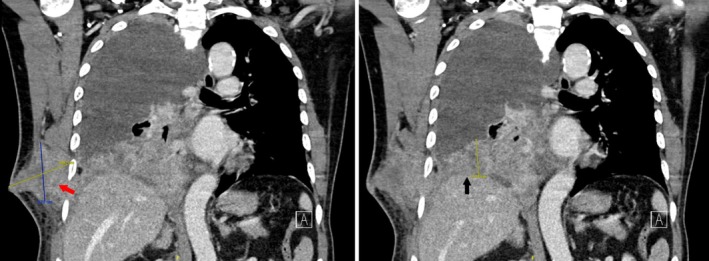

A 78-year-old man with a history of haemothorax developed a chest wall mass at the site of a previous chest drain 2 months ago. Imaging revealed a right lung mass with pleural involvement and a soft tissue tract to the chest wall. Histology confirmed squamous cell carcinoma. This case highlights a rare instance of metastasis via a chest drain tract.